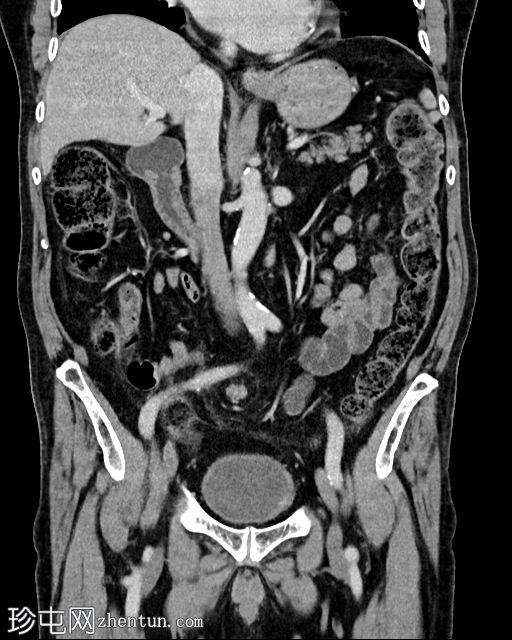

冠状位增强扫描(门静脉期)

乙状结肠系膜呈漩涡征,乙状结肠袢扩张且冗长。乙状结肠和直肠下游塌陷。结肠上游扩张。小肠袢未见扩张。乙状结肠系膜少量积液,脂肪条索状改变。腹膜内未见游离气体。